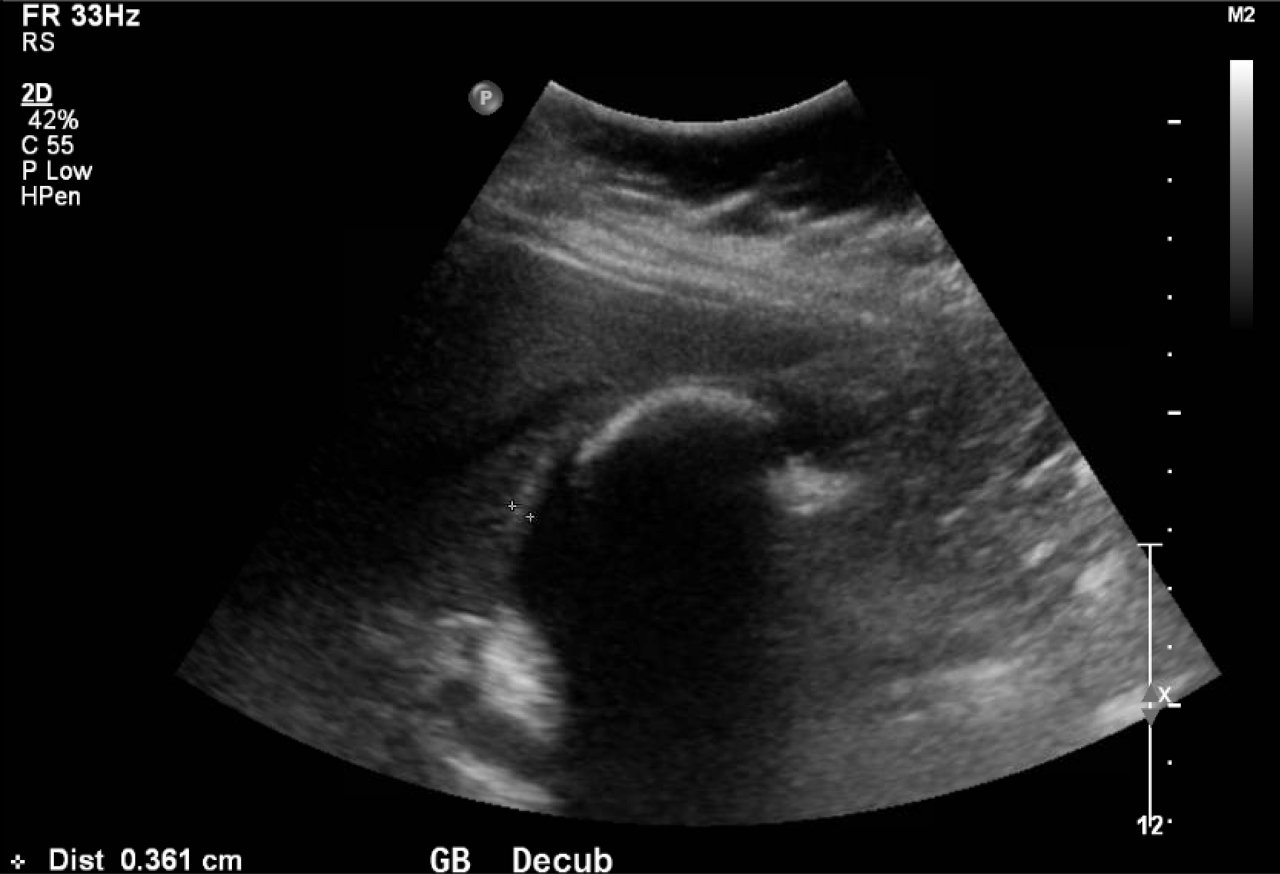

Abdominal ultrasound showed the classic presentation of the Wall-Echo-Shadow (WES) sign. The superficial aspect of the gallbladder wall is represented by a hyperechogenic curve. Below this, bile fluid is represented by hypoechogenicity. Underneath the bile fluid is the echo of the dense border created by the collection of gallstones, represented by a hyperechogenic curve. Due to the high density of the gallstones, nothing deeper can be visualized (including other gallstones or the far end of the gallbladder); this is the shadow.

The WES sign, first described in the early 1980s, is a clear way of identifying cholelithiasis when the condition has progressed to fill the entire lumen of the gallbladder.1 In this case, the lumen of the gallbladder looks hypoechogenic relative to the surrounding tissue, much like an empty gallbladder. This is due to the border of the dense stones opposing the near wall of the gallbladder casting a shadow over everything distal to the stones. These key visualization techniques decrease non-visualization of chronic cholelithiasis.2,3,4 In most cases, WES sign is sufficient to diagnose cholelithiasis. Of note, “porcelain gallbladder” or collapsed duodenum can have the potential produce similar ultrasonographic findings.4,5